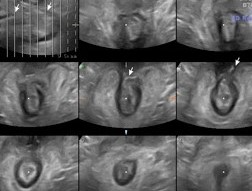

Επικαλυπτική σφιγκτηροπλαστική. Σχηματική απεικόνιση (Ευγενική παραχώρηση Dr. V. Penopoulos)

Πράσινο βέλος - εσωτερικός και κίτρινο βέλος - εξωτερικός σφιγκτήρας μετά επιμελή αποκόλληση (Ευγενική παραχώρηση Dr. V. Penopoulos)